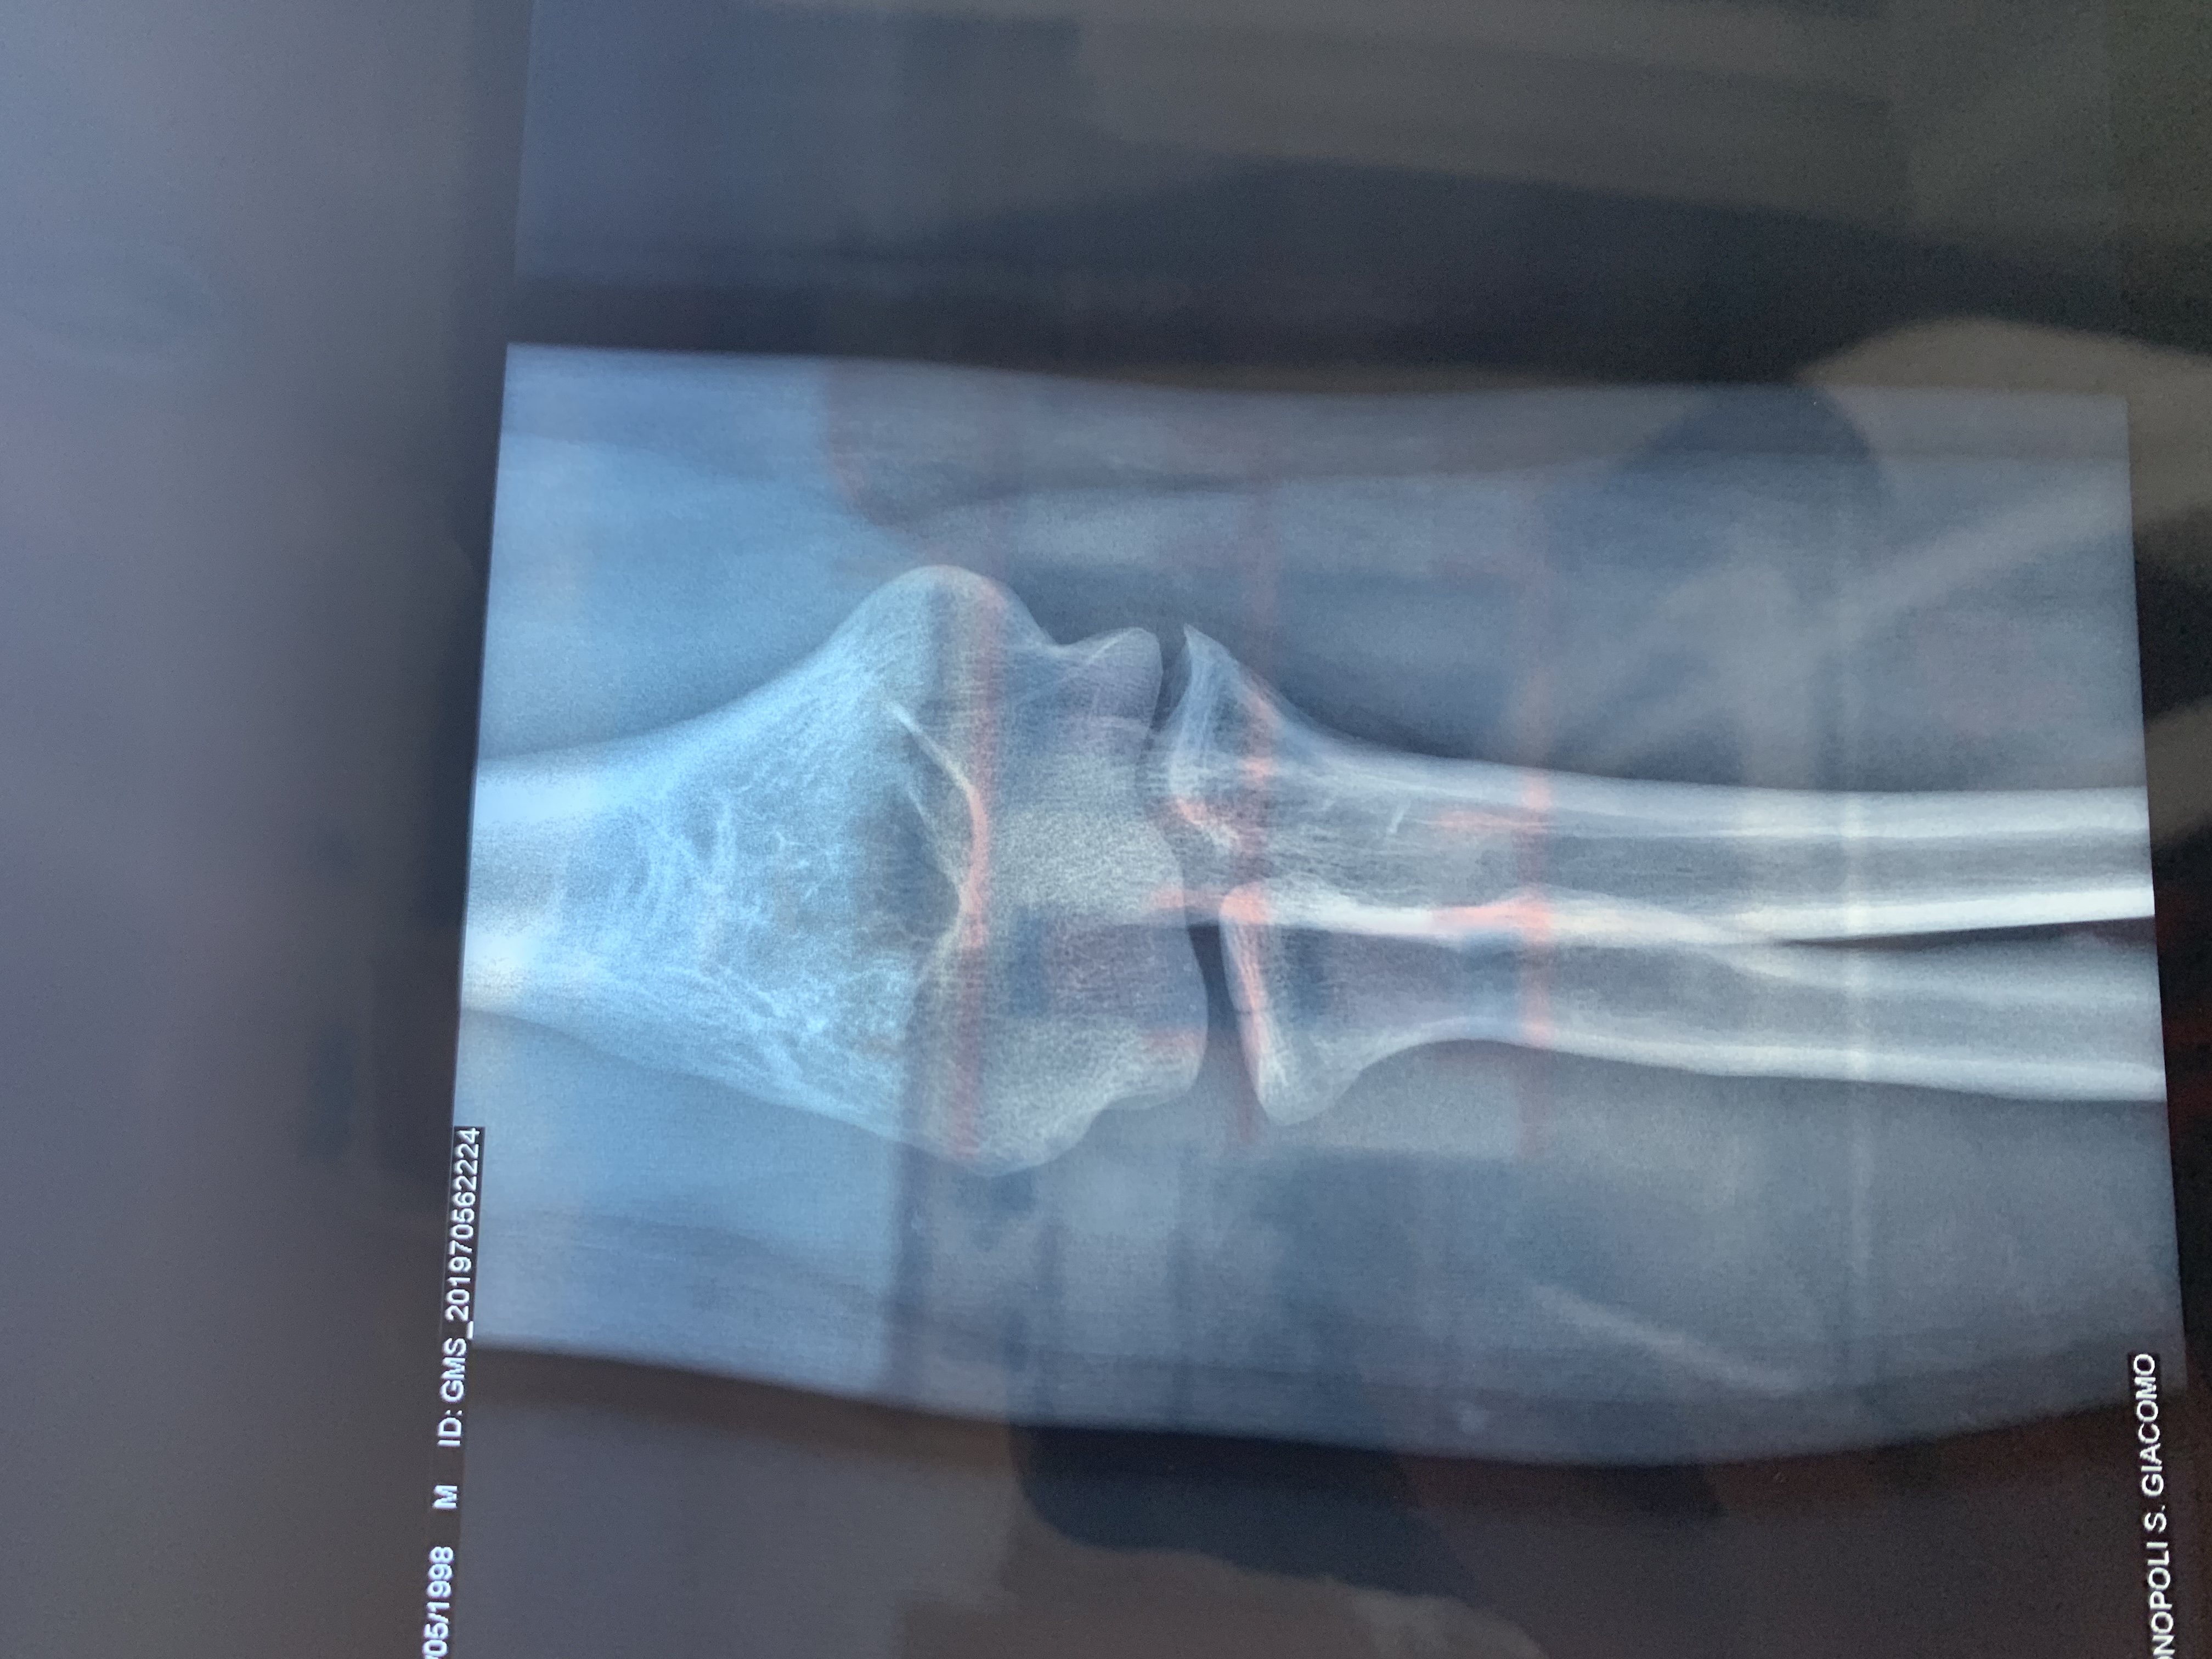

Commento file: Seconda lastra

5FEF7CE9-7B22-40B7-95AF-A3A18FFA94A8.jpeg

Buonasera, ieri in data 21 maggio mentre giocavo a calcetto tra amici, purtroppo durante un contrasto sono caduto.. il peso del corpo è caduto tutto sul mio braccio destro, ho sentito in un primo impatto un dolore lancinante, però subito dopo ho continuato a giocare a mia insaputa della gravità del problema, ho continuato a giocare per circa 1 ora, senza alcun evidente problema. Tornato a casa applico una pomata antinfiammatoria e una fascia che immobilizza non totalmente il gomito. In mattina mi reco in pronto soccorso,dagli esami rx viene rilevata una frattura composta del capitello radiale dx con componente intra-articolare con seguente visita ortopedica con immediata doccia gessata per 25 giorni . L

Ortopedico mi ha consigliato di ritornare entro una decina di giorni per altro controllo ,la

Mia domanda per voi è c’è la possibilità che mi venga tolto il gesso e applicata una fascia ? Inoltre il mio dubbio consiste nel riprendere la piena mobilità dell articolazione del gomito visto che tra due mesi ho un impegno lavorativo importante. In allegato i referti rx . Grazie attendo buone nuove